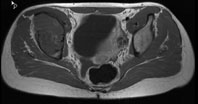

Die Röntgenuntersuchung von Becken/Hüfte zeigt eine septierte geographische Osteolyse in der Ala und im Korpus des Os Iliums rechts. Das Röntgenbild und die Aufnahmen der nachfolgenden MRI-Untersuchung sehen Sie hier:

T2 FS, axial, 5 mm

Bild vergrössern